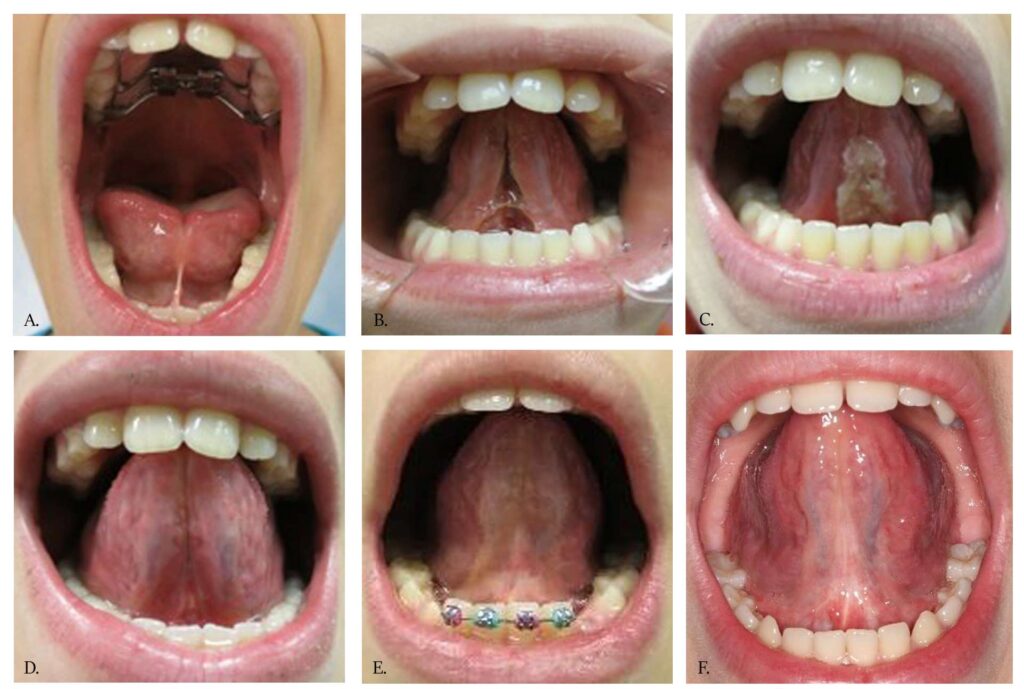

The Tongue-Tie FUNCTIONAL RELEASE is illustrated by clinical cases in Figures 1-3. Note both the immediate and the long-term improved mobility and lift of the tongue. The highly controlled hemorrhage, sealed lymphatics and significantly reduced zone of thermal impact result in less edema and discomfort to the patient. Magnification during the frenectomy is highly recommended as large blood vessels and nerves are in close proximity to the surgical site. Authors prefer to use topical anesthesia to increase the reliability of tongue function during the release. Topical anesthesia does not restrict tongue movement during the procedure when real-time assessment takes place.